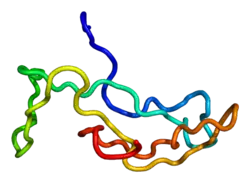

Glycoprotein hormones, alpha polypeptide is a protein that in humans is encoded by the CGA gene.[5]

The gonadotropin hormones, human chorionic gonadotropin (hCG), luteinizing hormone (LH), follicle-stimulating hormone (FSH), and thyroid-stimulating hormone (TSH) are heterodimers consisting of alpha and beta subunits (also called chains) that are associated non-covalently. The alpha subunits of these four human glycoprotein hormones are identical; however, their beta chains are unique and confer biological specificity. The protein encoded by this gene is the alpha subunit and belongs to the glycoprotein hormones alpha chain family.[6]